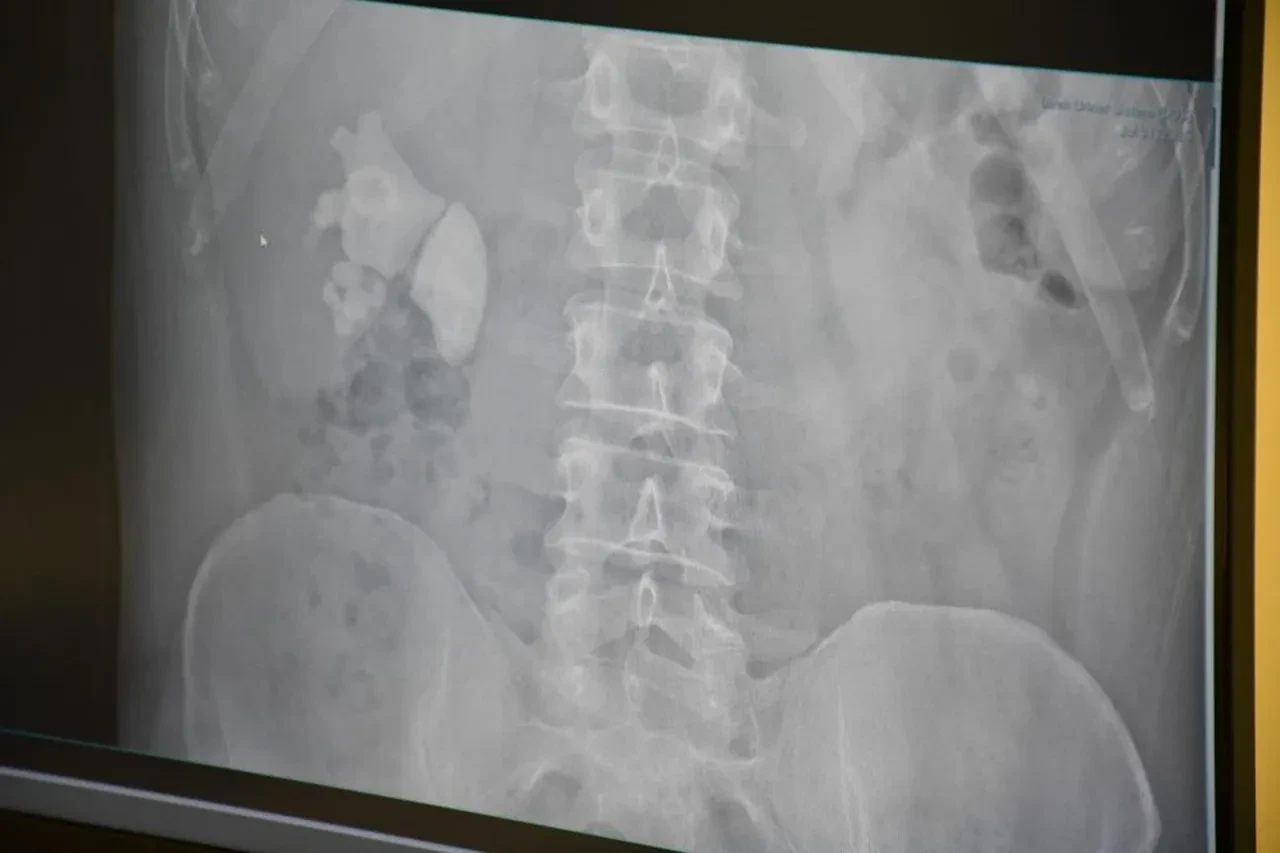

Akdağmadeni ilçesinde benzerine az rastlanır bir sağlık olayı yaşandı. Serhat Evran isimli vatandaş, dayanılmaz ağrılarla hastaneye başvurdu. Evran’ın detaylı tetkiklerinin yapılmasının ardından böbreğinde 100 taneye yakın taş tespit edildi.

Kocamanoğlu, "Yaptığımız incelemede sağ böbreğin tamamını dolduran taşları vardı. Hastayla görüşerek bu tür büyük taşlarda büyük bir cerrahi olabileceğini ve hastanın birkaç delikten girerek, sırttan delerek ameliyat yapılması gerektiğini söyledik. Hastamız kabul etti. Çarşamba günü hastanın ameliyatını yaptık. Tek delikten girerek neredeyse tamamını temizledik. Bugün de hastamızı sağlıklı bir şekilde taburcu edeceğiz" dedi.